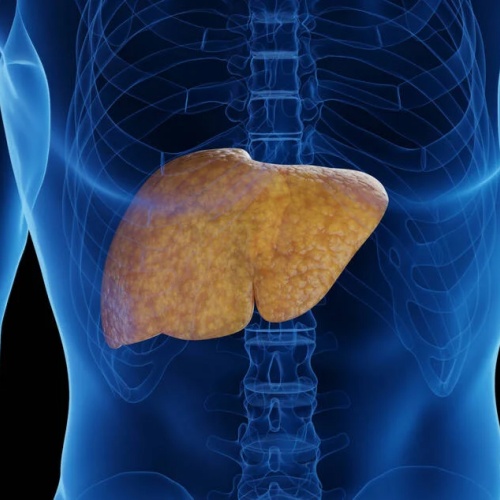

代谢相关脂肪性肝病(MASLD)在全球范围内的患病率持续上升,约三分之一成年人受到影响。当肝脏脂质沉积进一步引发炎症反应时,疾病可进展为代谢相关脂肪性肝炎(MASH)。MASH的潜在风险包括:肝纤维化逐渐形成,发展为肝硬化,甚至进展为肝细胞癌。

减少肝脏脂肪沉积。

通过上述神经通路,FGF21在肝脏中产生多方面的代谢效应:抑制肝细胞脂质生成(脂肪生成减少),降低肝脏甘油三酯水平,提高整体能量消耗,改善胰岛素敏感性,促进体重下降。

这些变化有助于减轻脂肪肝及其炎症反应。

肝脏脂肪含量显著下降,

肝纤维化程度减轻,

即使在不健康饮食条件下仍然有效。